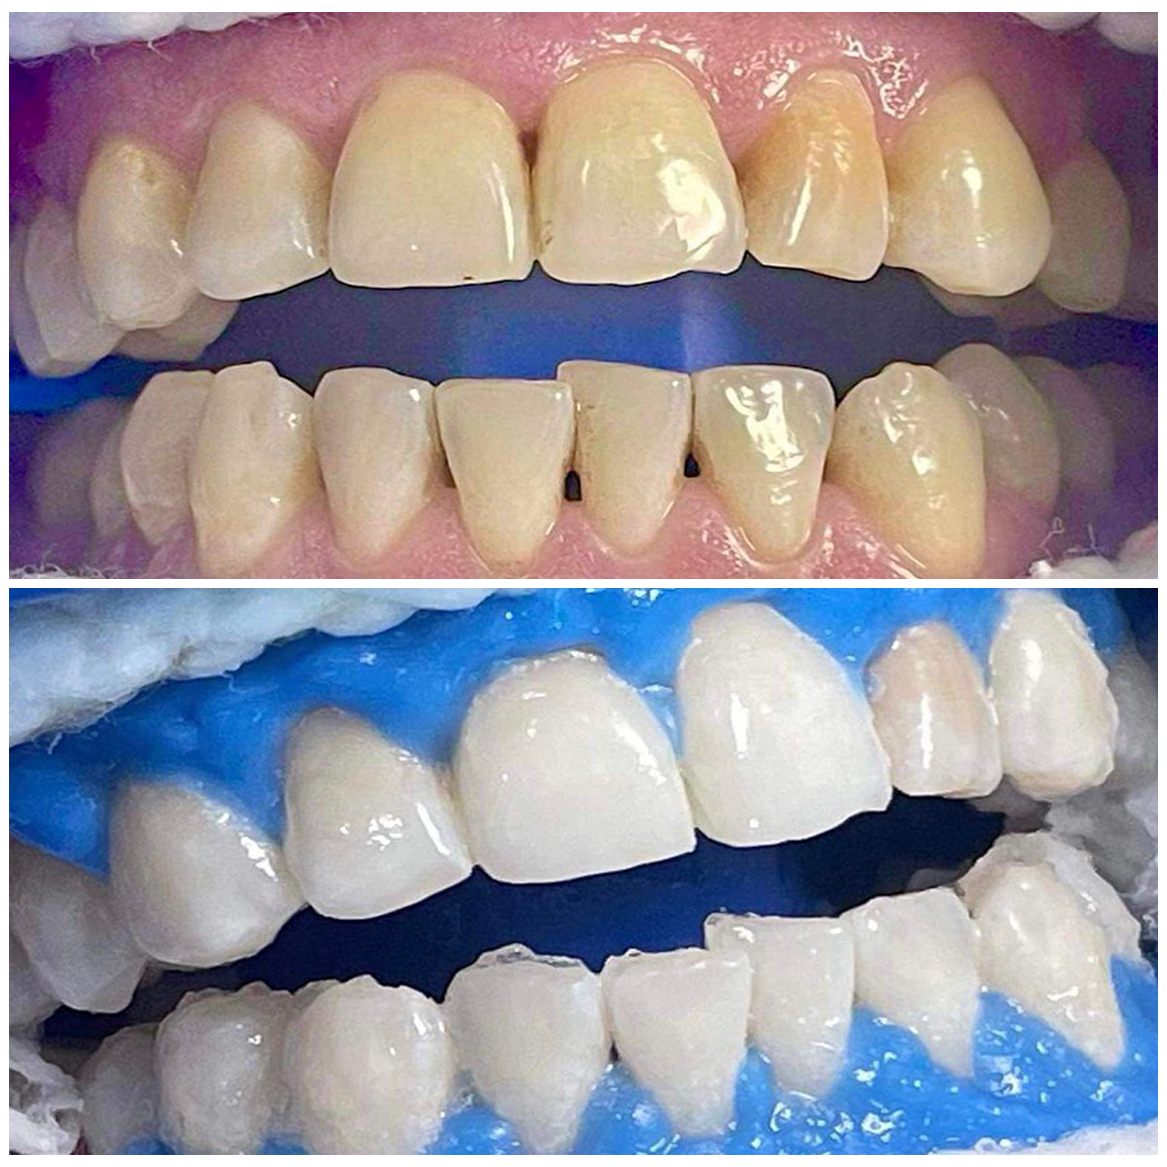

Hollywood Smile

Facettes esthétiques en disilicate de lithium apres un assainissement parodontal et une chirurgie d’élongation coronaire

Blanchiment dentaire

Blanchiment dentaire : élimination des taches pour des dents plus claires.